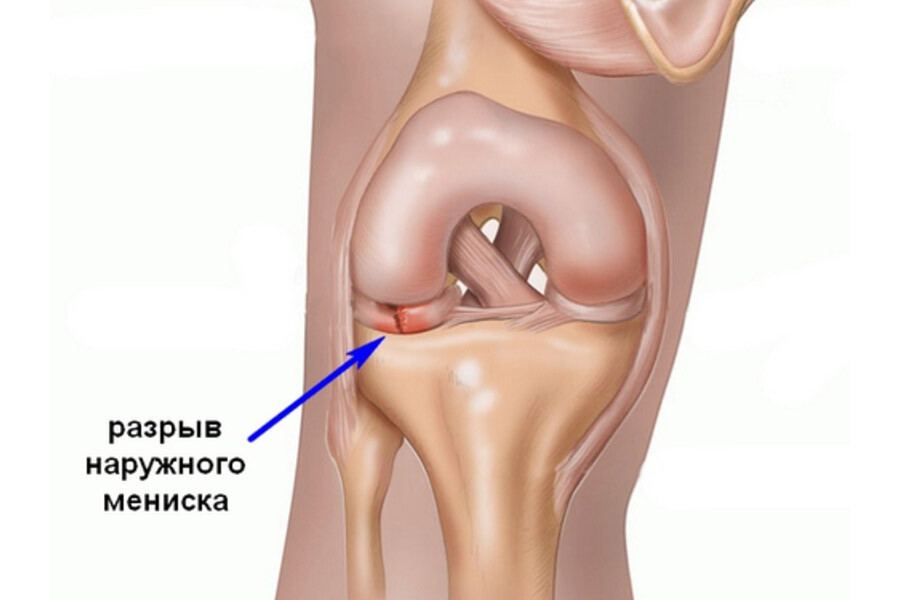

Анатомические изображения менисков и коленного сустава

Раздел: Иллюстрированные советы